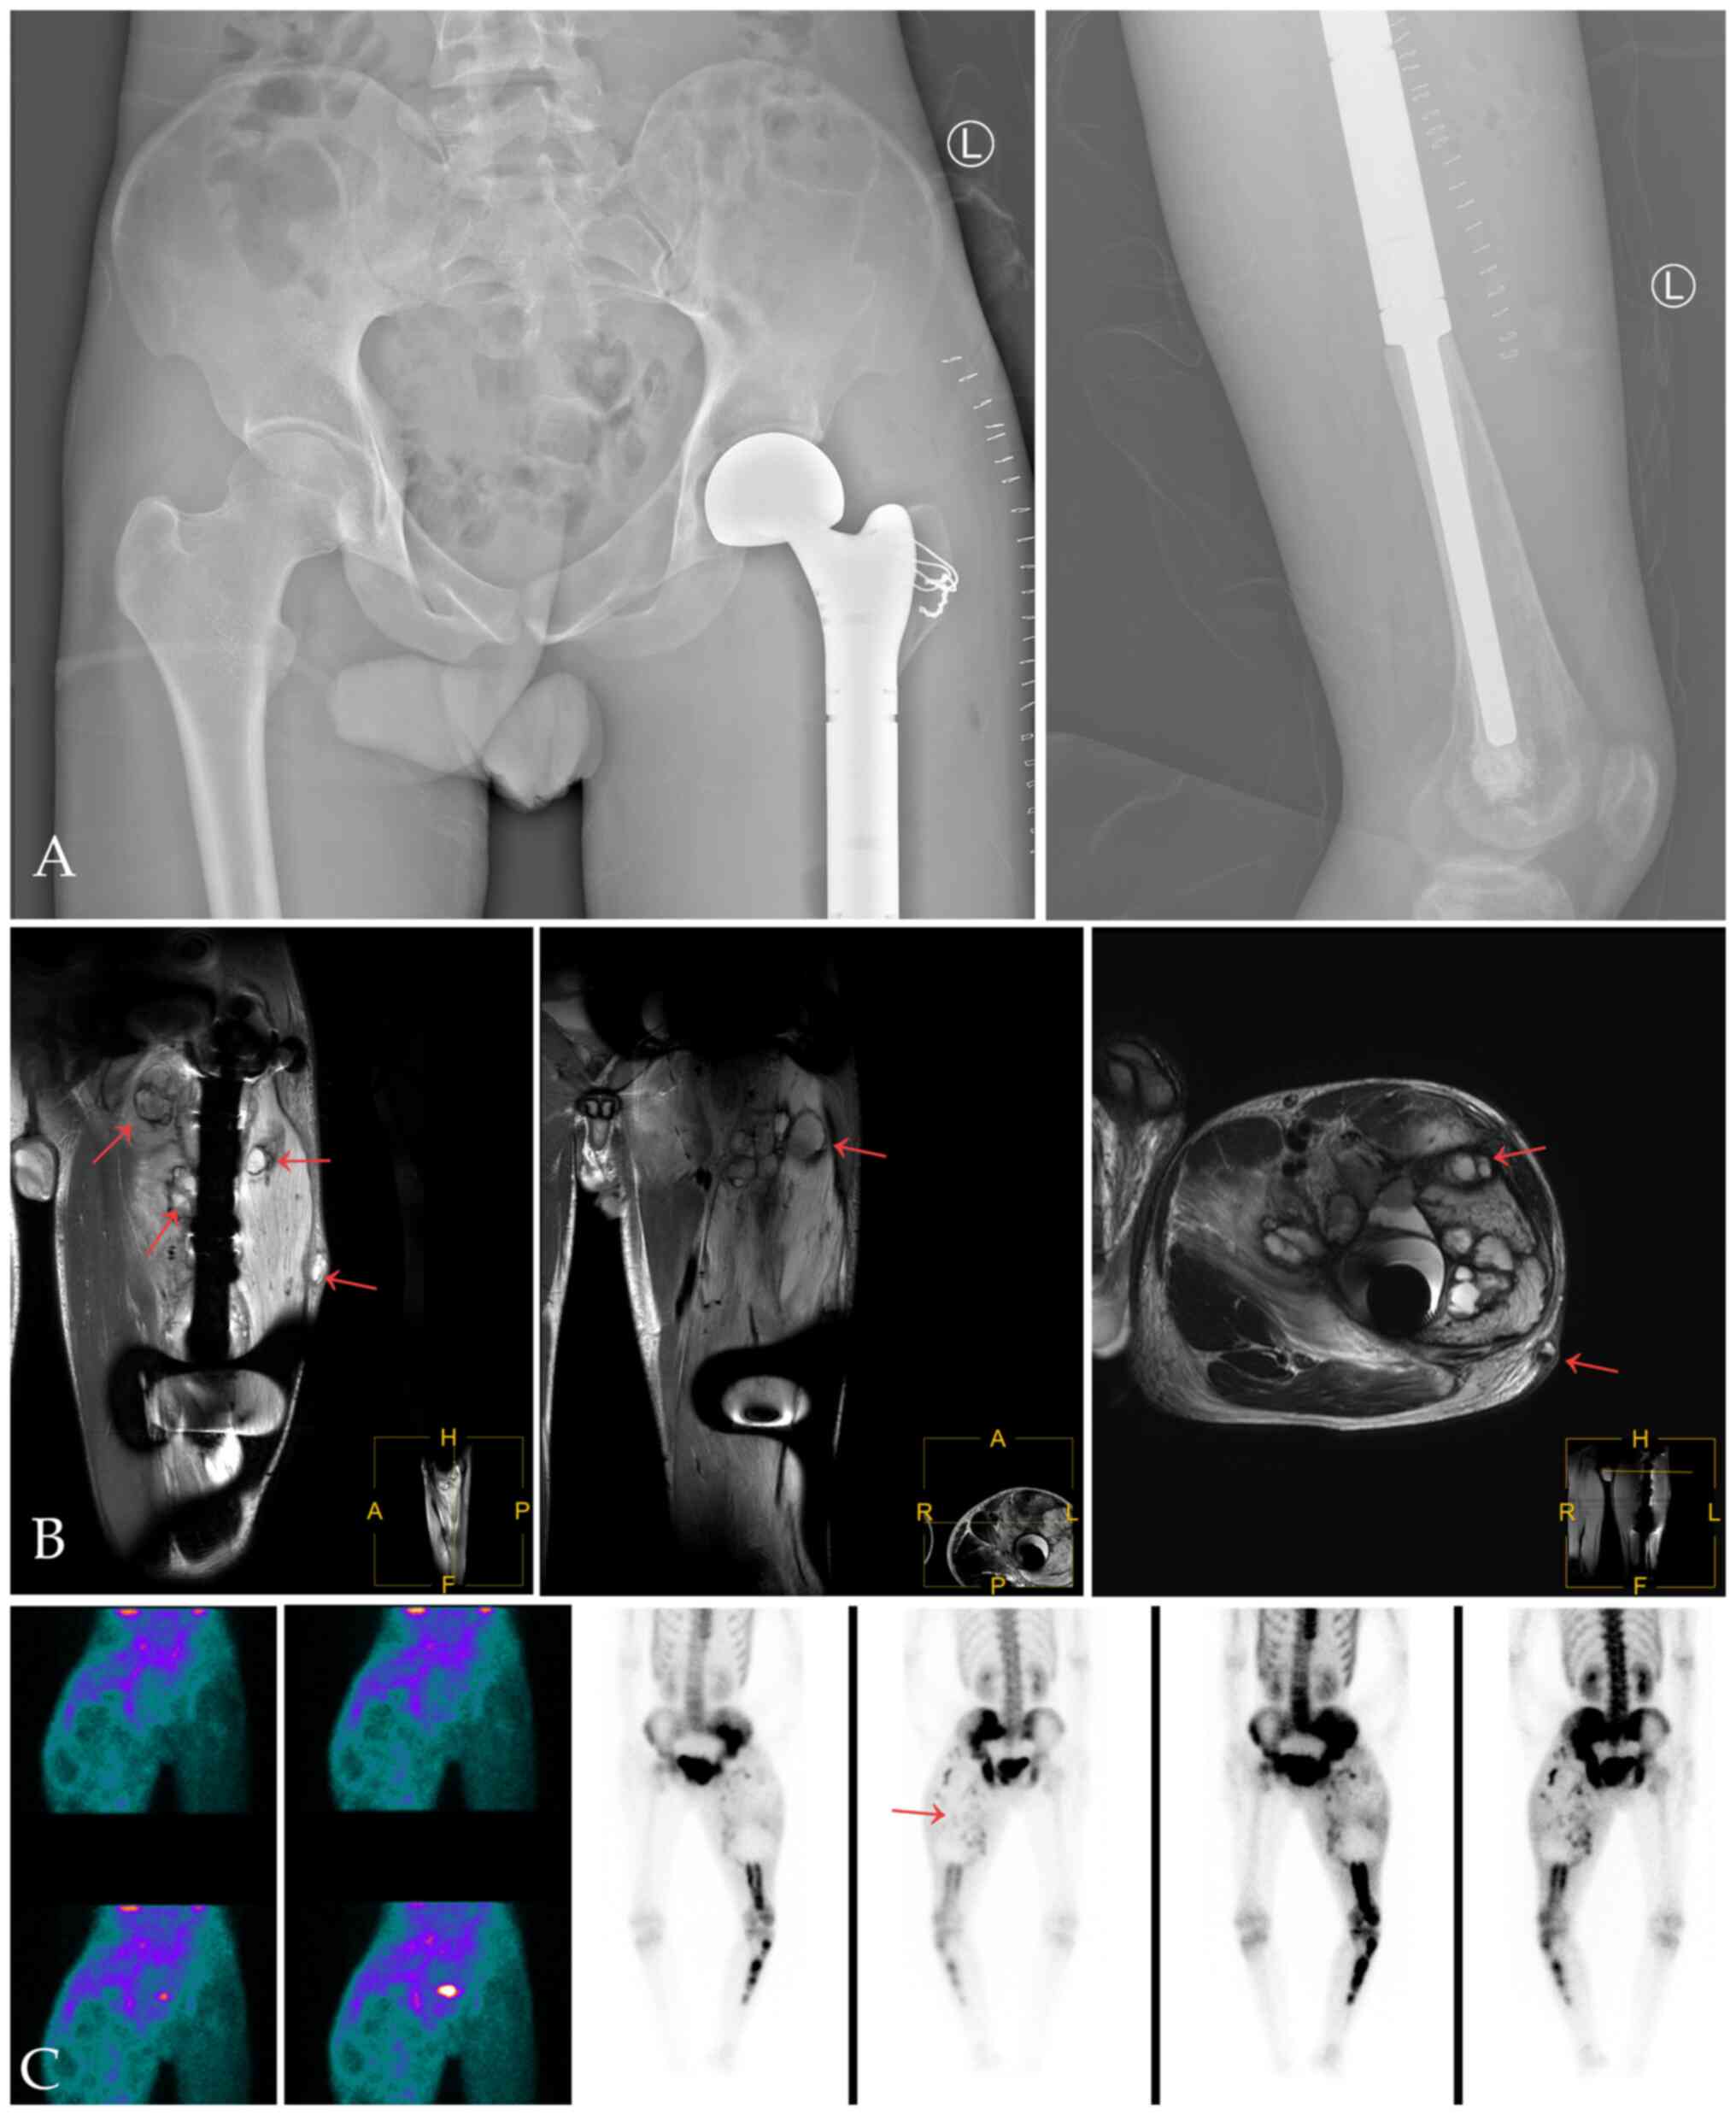

X-ray and CT of the left femur showed abnormal density of the left femur and the bone marrow cavity of the left hip, upper tibia and sacrum, and bone destruction of the anteromedial cortex of the left femur and formation of surrounding soft tissue masses (Fig. 1A-C). The possibility of malignancy was considered. MRI showed multiple bone destruction areas occupying most of the space of the marrow cavity with hypointensity on T1-weight imaging (T1WI), heterogeneous enhancement on contrast-enhanced T1WI, heterogeneous iso- and hyper-intensity on T2WI, and heterogeneous signal intensity on T2-weight spectral attenuated inversion recovery (T2W-SPAIR).

Figure 1

X-ray and CT of fibrous dysplasia of bone with malignant transformation. (A) X-ray and (B) bone window CT images showed low-density areas of multiple bone destruction and ground-glass high density in the left hip and upper femur bone marrow cavity. (C) Venous phase (a phase of contrast-enhanced CT) of soft tissue window of the left femur shows destruction of cortical bone with formation of soft tissue masses around the left upper medial femur with heterogeneous enhancement.

These features indicated local bone destruction, swelling of surrounding soft tissue and soft tissue invasion (Fig. 2A and B). In the upper left femur, an irregular mass was seen in front of the upper left femur, which broke through the cortex and protruded into the surrounding soft tissue (Fig. 2C). 99mTc-MDP three-phase bone imaging was recommended to confirm the blood supply and abnormal uptake of 99mTc-MDP. The areas of bone and marrow surrounding the greater trochanter and the neck of the left femur showed increased blood perfusion on the perfusion and blood pool phase, while bone marrow destruction areas in MRI showed higher amounts of blood perfusion in the upper femur (below the greater trochanter) (Fig. 3A and B). However, the levels of tracer uptake of the two areas were reversed in the delayed phase and were clearer on tomography. The other tracer uptake lesions in the left pelvic and lower limb bone corresponded to an ill-defined radiolucent lesion on X-ray (Fig. 3C and D).

Figure 2

MRI of fibrous dysplasia of bone with malignant transformation. (A and B) Axial T1WI and T2WI and contrast-enhanced coronal T1WI showed destruction of the upper part of the left femur and an irregular soft tissue mass, with hypointensity on T1WI, heterogeneous iso- and hyper-intensitye on T2WI, heterogeneous enhancement contrast-enhanced T1WI and heterogeneous signal intensity on T2W-SPAIR. (C) Diffusion of the lesion was limited. The left femur, tibial medullary cavity shows multiple of circular, flaky bone destruction. Diffusion-weighted imaging showed heperintensity. T1WI, T1-weighted imaging; T2WI, T2-weighted imaging; T2W-SPAIR, T2-weight spectral attenuated inversion recovery.

Figure 3

99mTc-MDP three-phase bone imaging of fibrous dysplasia of bone with malignant transformation. (A) Blood perfusion phase showed abnormal high blood perfusion in the right thigh. (B) Blood pool phase showed abnormal radiotracer concentration in the corresponding area of the soft tissue. (C) Whole body bone imaging and (D) tomography showed extensive abnormal concentration of radioactivity in the left pelvis (ilium, pubic bone and ischium) and left lower limb (femur and tibia). By contrast, bone and marrow around the greater trochanter (yellow arrow, about the same height as the bladder) showed less blood perfusion on the perfusion phase but more tracer uptake on the delayed phase, and the opposite is true for the lesion below the greater trochanter (red arrow).

After the final diagnosis, the patient received chemotherapy with epirubicin 50 mg + vincristine 2 mg + methotrexate 10 g, and the process was successful. Subsequently, 2 weeks later (22 June 2018), left femur tumor segment resection and hip replacement were performed (Fig. 7A), and postoperative histological examination confirmed that the bone tumor tissue and distal femoral medullary cavity were consistent with fibrosarcoma. In September 2018, ~3 months after the operation, a surgical biopsy was performed on a mass resected from the surface of the left thigh because of suspicion of local tumor recurrence (Fig. 7B and C). Pathological examination showed recurrence of the left femur fibrosarcoma, and surgical resection and symptomatic treatment were performed again. In March 2019, another operation of the left hip disarticulation was scheduled for tumor resection following further local recurrence. The operation was successful without obvious postoperative acute complications.

Figure 7

Postoperative and follow-up images. (A) X-ray images showed changes after left femur tumor segment resection and hip replacement. The upper segment of the left femur and surrounding local soft tissue were removed and an artificial femur was fixed internally. (B) MRI at 3 months after surgery showed multiple nodular lesions (red arrows) in the muscle and subcutaneous tissue around the artificial femur. (C) 99mTc-MDP three-phase bone imaging showed high blood perfusion and increased tracer uptake of the new soft tissue lesions, although these increases were lower compared with other FDB lesions in the delayed phase.